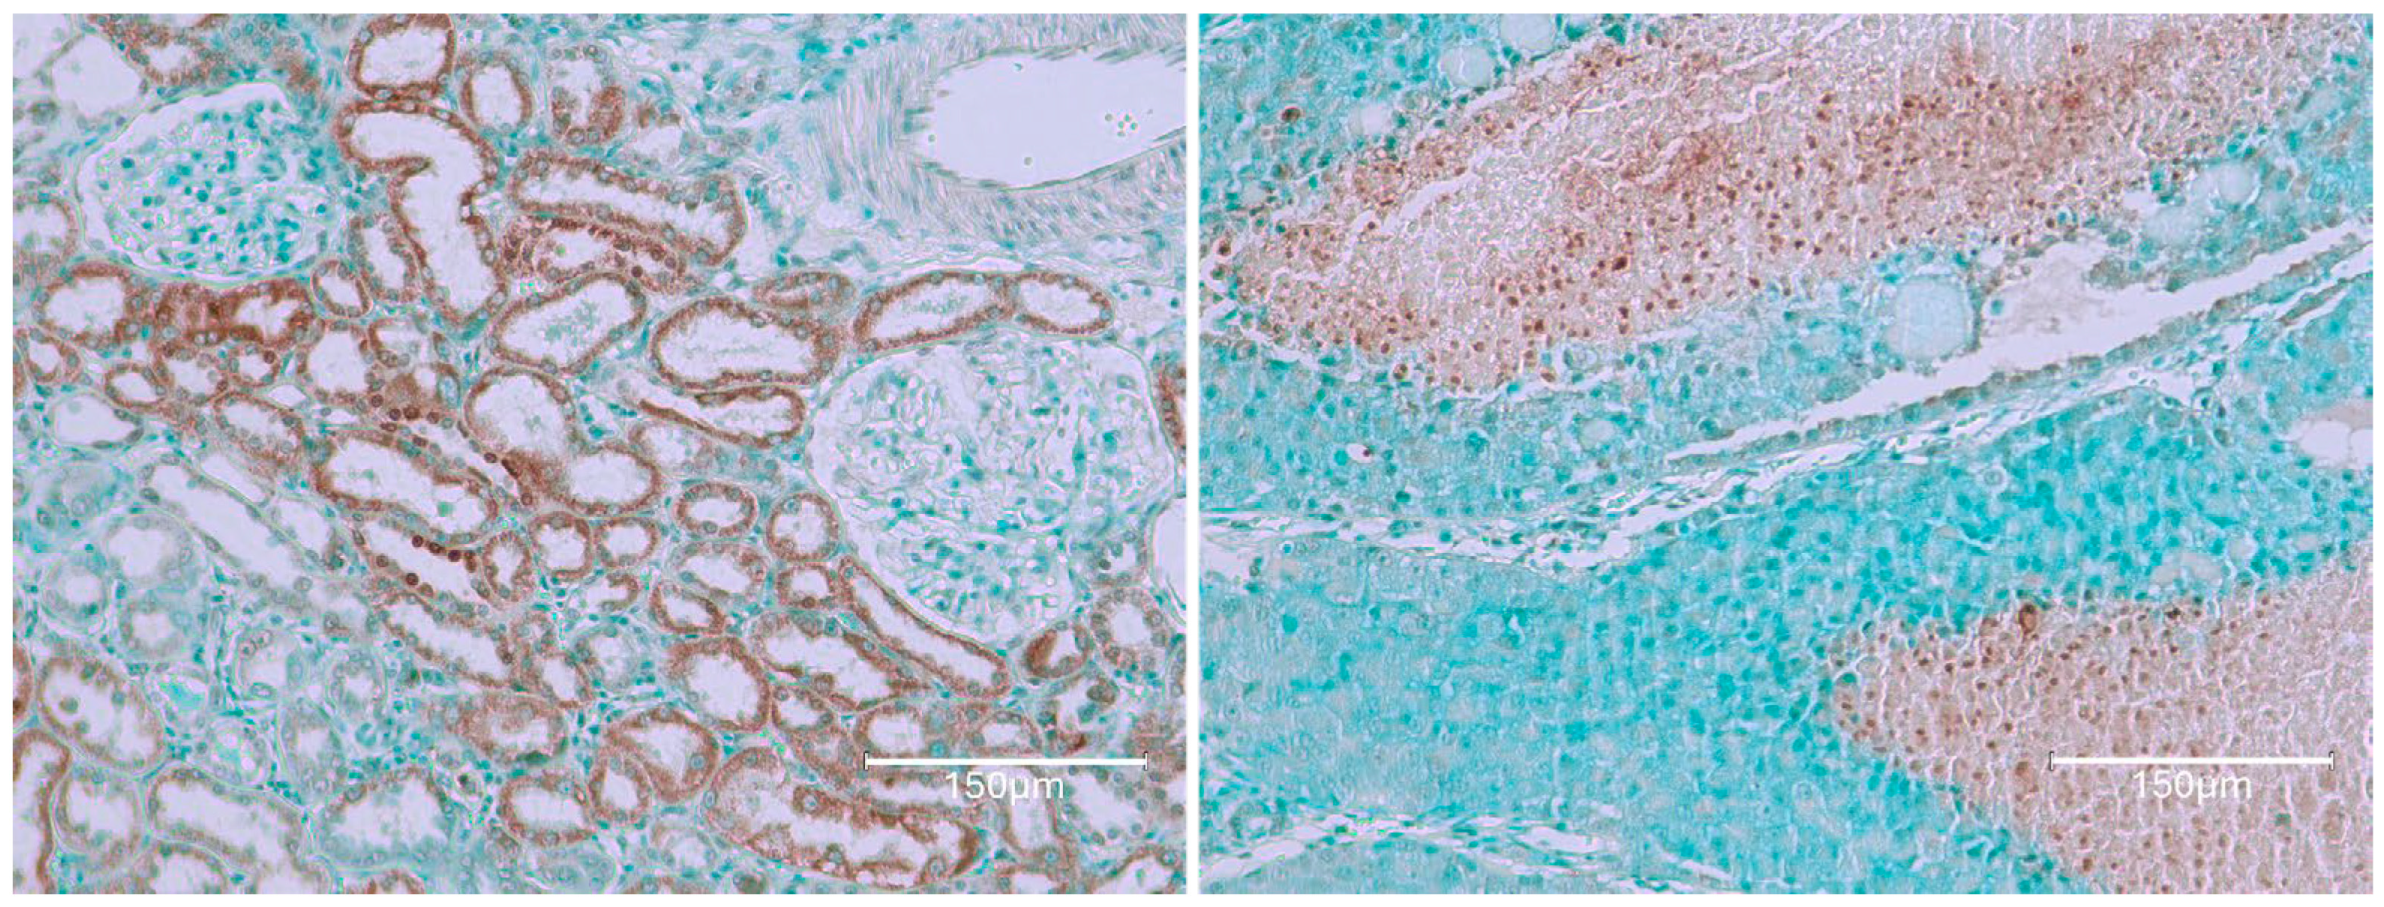

2.1. Carcinogenic Dose of Ochratoxin for Life for Three Fischer Rats

2.2. Low-Dose Ochratoxin for Life for Three Fischer Rats

2.3. Fischer Rat—Second Year OTA Only

2.4. Dark Agouti Rat—SINGLE RAT

- Miljkovic, A.; Mantle, P. Renal apoptosis in the mycotoxicology of Penicillium polonicum and ochratoxin in rats. Life 2022, 12, 352. [Google Scholar] [CrossRef]